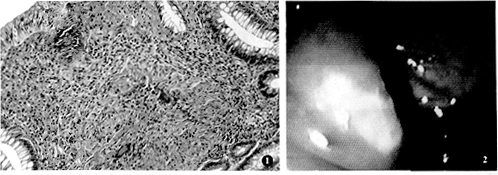

摘要 目的 探讨早期肠结核的病理变化。方法 对结肠镜诊断的3 例早期肠结核进行分析。结果 早期肠结核的病理特征是:回盲部粘膜充血、水肿或( ) 糜烂;纤维素样渗出及霜样白苔,回盲瓣红肿变形;无溃疡和息肉样增生;光镜下见粘膜层内结核结节,无溃疡和肉芽、纤维组织增生。结论 认识早期肠结核的病理变化,对促进早期肠结核的诊断和完善肠结核的病理分型具有重要意义。

Abstract Objective To probe into the characteristics of pathological changes of earlyintestinal tuberculosis. Method Three cases of early intestinal tuberculosis proved by colonoscopywere reported and analyzed. Result Hyperemia and edema of the ileocecal mucosa were found. Theinvolved mucosa looked friable and eroded, which was covered by fibrinopurulent exudatesor forsty white mucus. The ileocecal valve was edematous and deformed. Tuberculoustubercles were found in intramucosal tissue under microscopy. Neither ulceration norfiberous hypertrophy was found. Conclusion It shows important significance to recognize the pathologicalmanifestations of early intestinal tuberculosis for diagnosis of the disease.